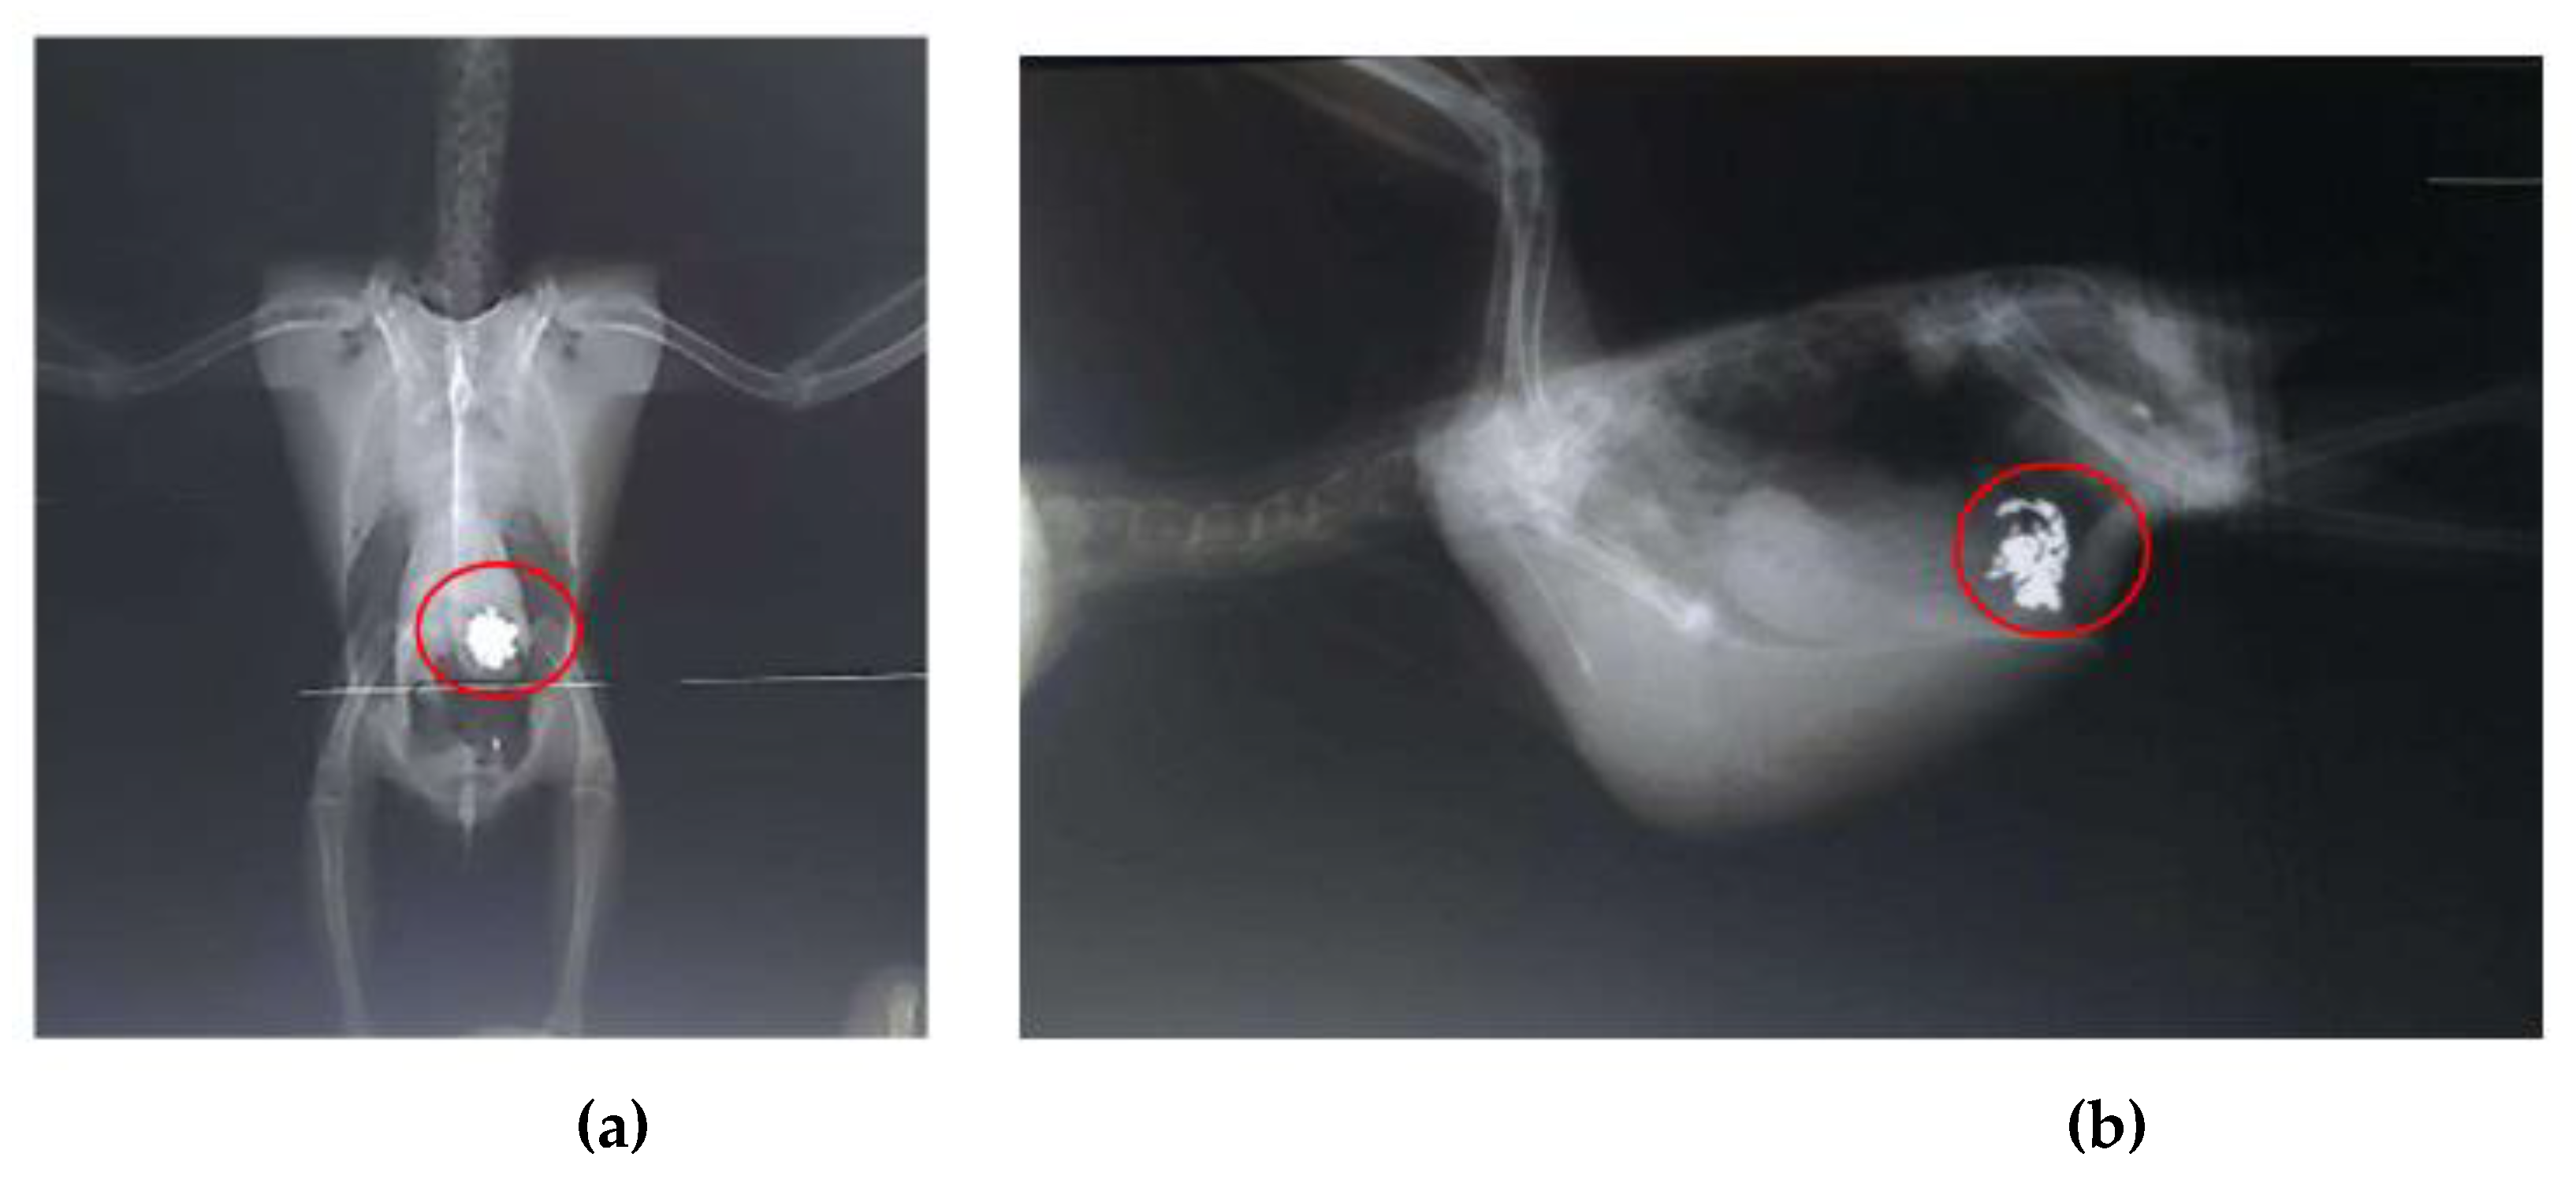

Radiographic examinations revealed a significant accumulation of radiopaque foreign bodies in the ventriculus of both birds, suggestive of metal ingestion (Figure 3A, B and Figure 4A, B). The hematological results are presented in Table 1.

Figure 4. Radiographic examination of the coelomic cavity of an Aratinga jandaya (bird 2). (a) Ventrodorsal projection – presence of a large quantity of radiopaque foreign bodies (outlined in red) in the ventricular region, suggestive of metal; increased radiopacity of the thoracic air sacs. (b) Right laterolateral projection – presence of radiopaque foreign bodies (outlined in red), also suggestive of metal.